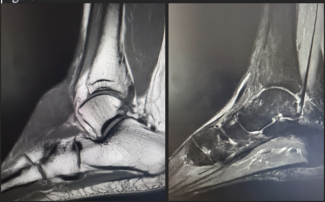

Total Talus Replacement

Jannani Krishnan, DPM; Bhavkaranjeet Kaur, DPM; James Brian Warne, DPM

Total talus replacement is emerging as a powerful salvage option for patients with advanced avascular necrosis (AVN), failed ankle arthroplasty, or end-stage ankle arthritis. This article explores the advantages of 3D-printed...